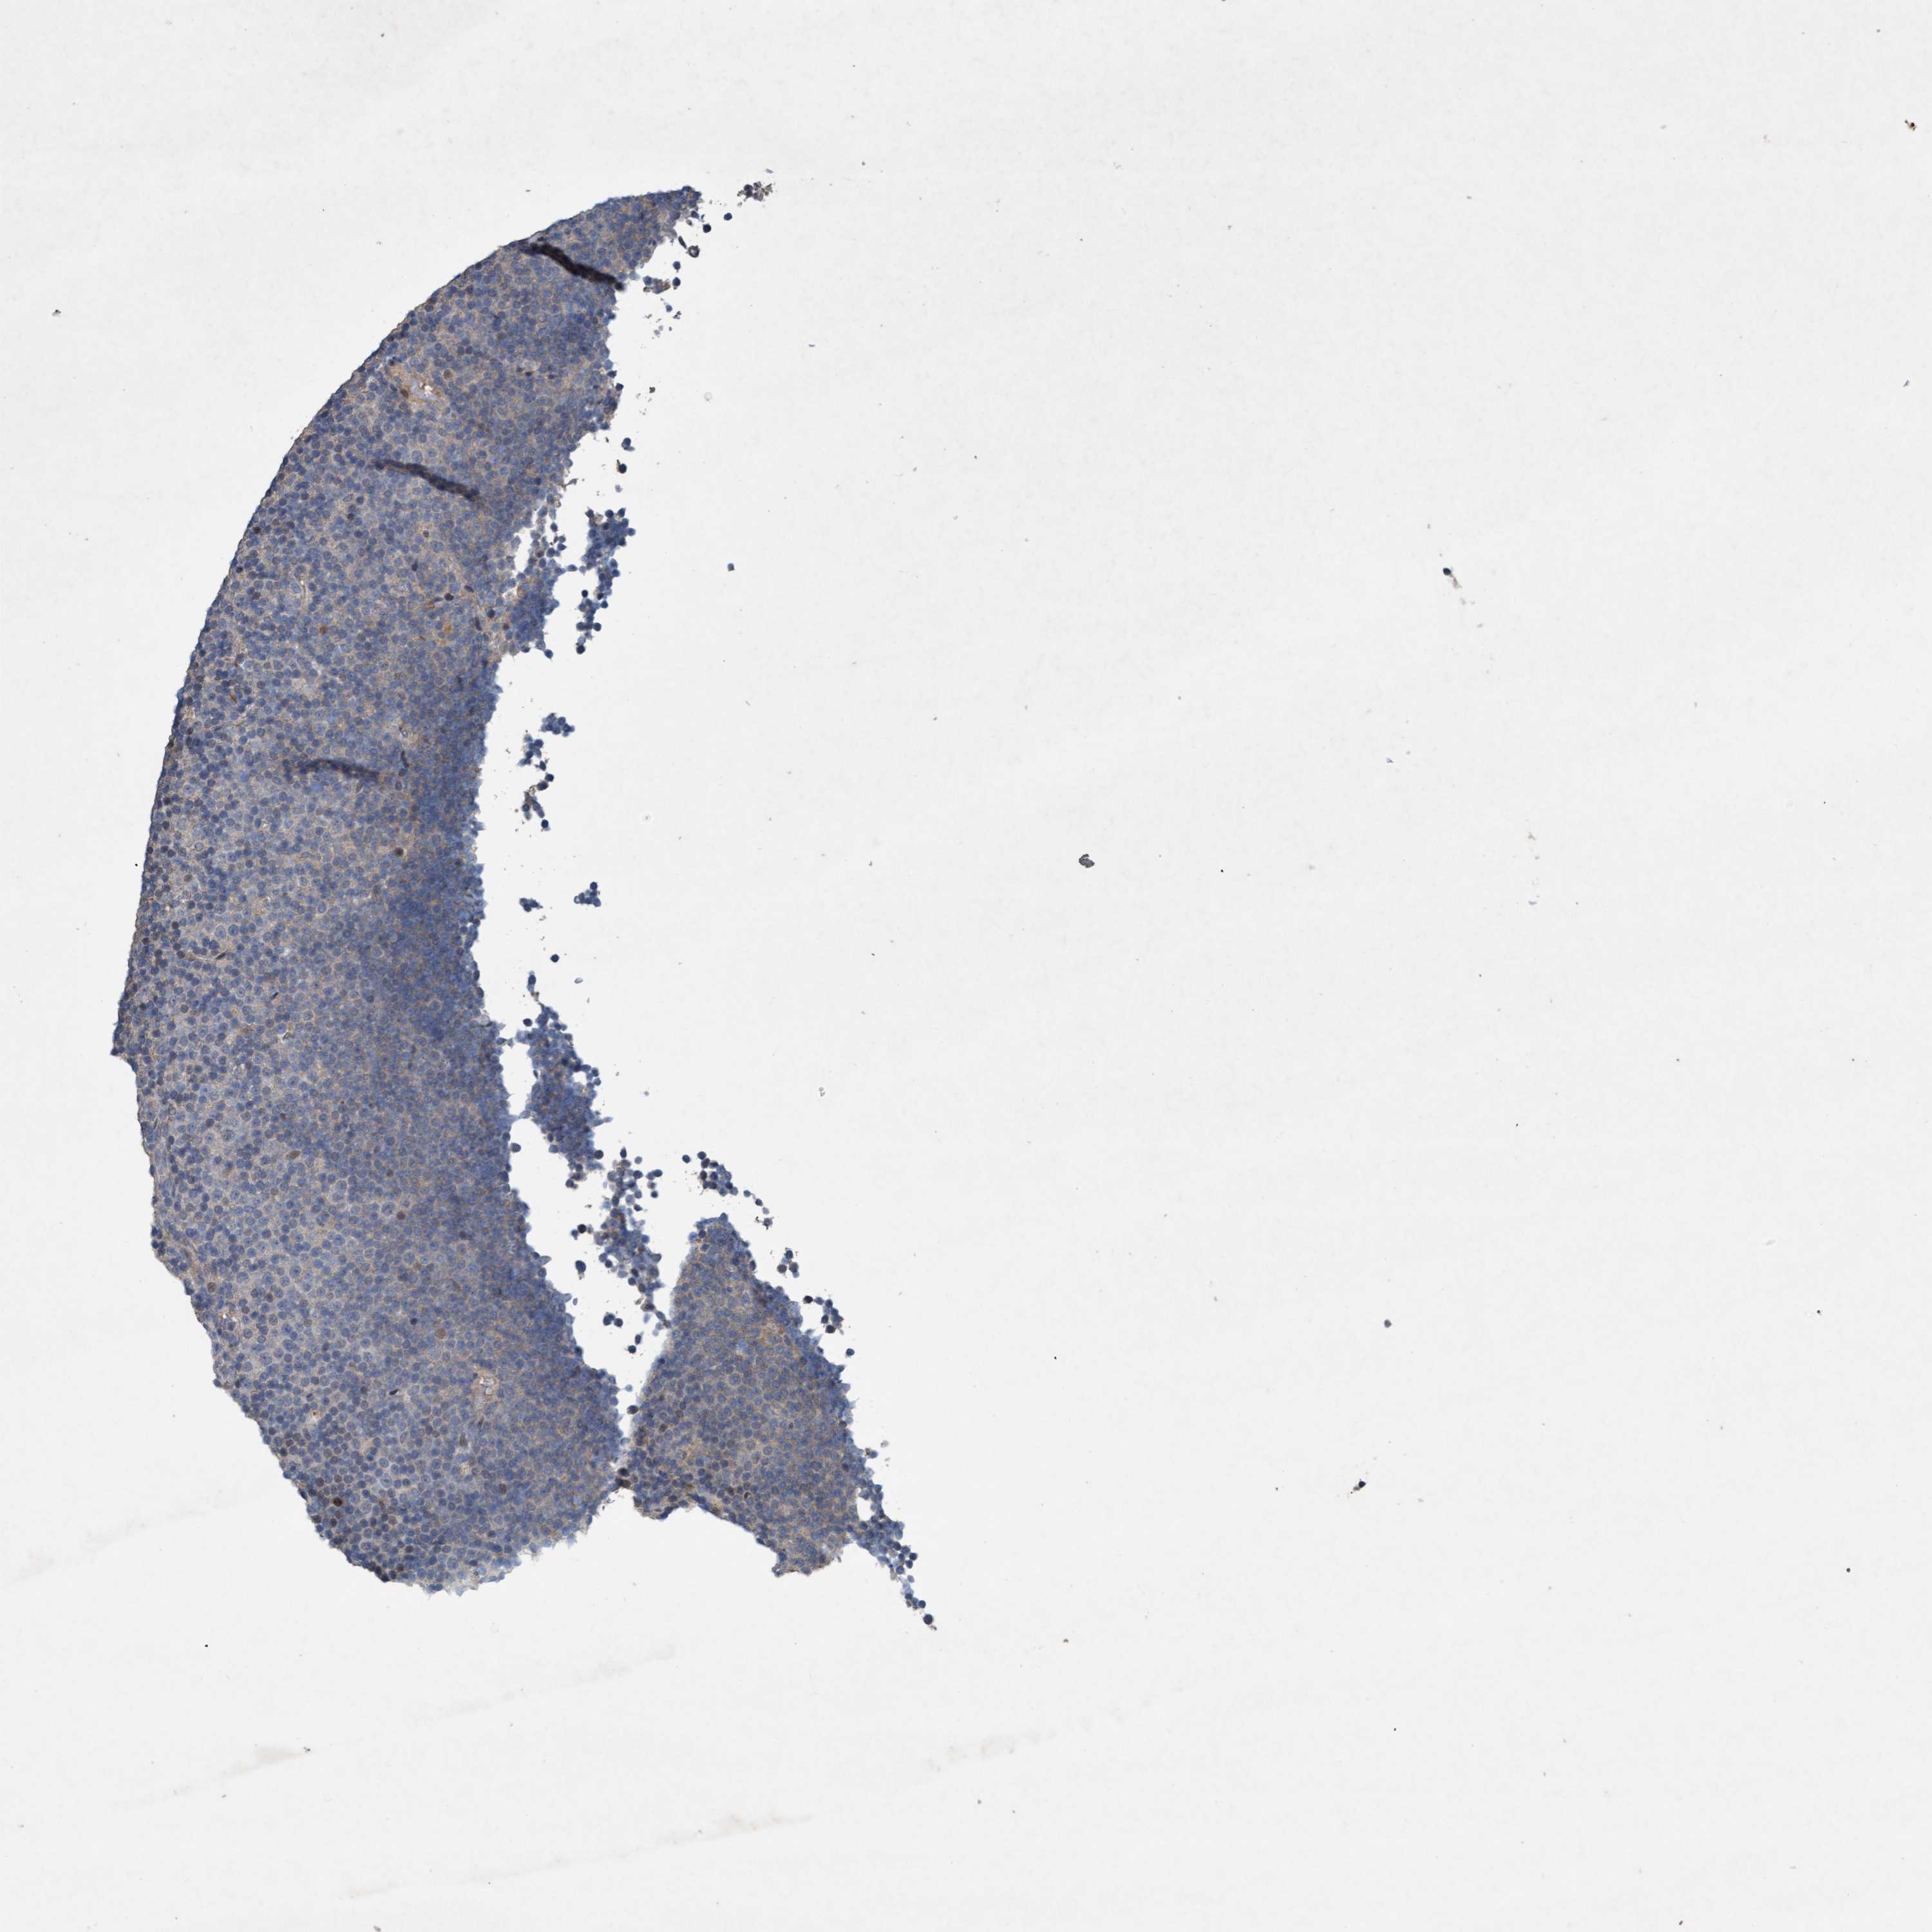

CANCER LYMPHOMA Show tissue menu

LYMPHOMA - Protein expressioni

A mouse-over function shows sample information and annotation data. Click on an image to view it in a full screen mode. Samples can be filtered based on level of antibody staining by selecting one or several of the following categories: high, medium, low and not detected. The assay and annotation is described here.

Each image is clickable and will lead to virtual microscopy that enables deeper exploration of all samples and also displays staining intensity scores, fraction scores and subcellular localization as well as patient and tissue information for each sample.

Antibody HPA023106

Staining

High

Medium

Low

Not detected

Intensity

Strong

Moderate

Weak

Negative

Quantity

>75%

75%-25%

<25%

None

Location

Nuclear

Cytoplasmic/membranous

Cytoplasmic/membranous,nuclear

Hodgkin's disease, NOS

Malignant lymphoma, non-Hodgkin's type, High grade

Malignant lymphoma, non-Hodgkin's type, Low grade